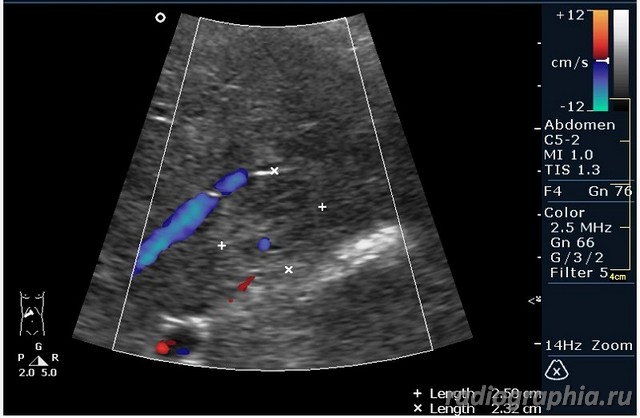

гемангиома,рядом питающий сосуд

Мне тоже нравится версия, что это - гемангиома.Нелли писал(а):гемангиома,рядом питающий сосуд